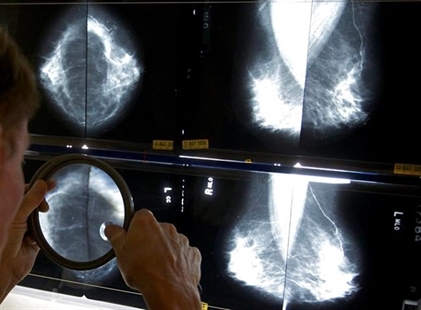

Researchers say a decades-old Canadian study that influenced breast cancer screening policy contained significant flaws in its approach, leading to a "substantial impact" on disease outcomes and potentially contributing to hundreds of "avoidable deaths" per year.

Two trials — collectively known as the Canadian National Breast Screening Study (CNBSS) — found that mammograms for women in their 40s did not reduce death rates from breast cancer.

They say more recent findings suggest there are benefits to mammography screening for women under 50, including a 2014 observational study that indicated that giving people mammograms in their 40s was associated with a 44 per cent reduction in breast cancer deaths.

The Canadian Task Force on Preventive Health Care doesn't currently recommend mammograms for people aged 40 to 49, unless a pre-existing factor puts them at a higher-than-average risk — for example, if a family member had breast cancer or if they have the BRCA gene.